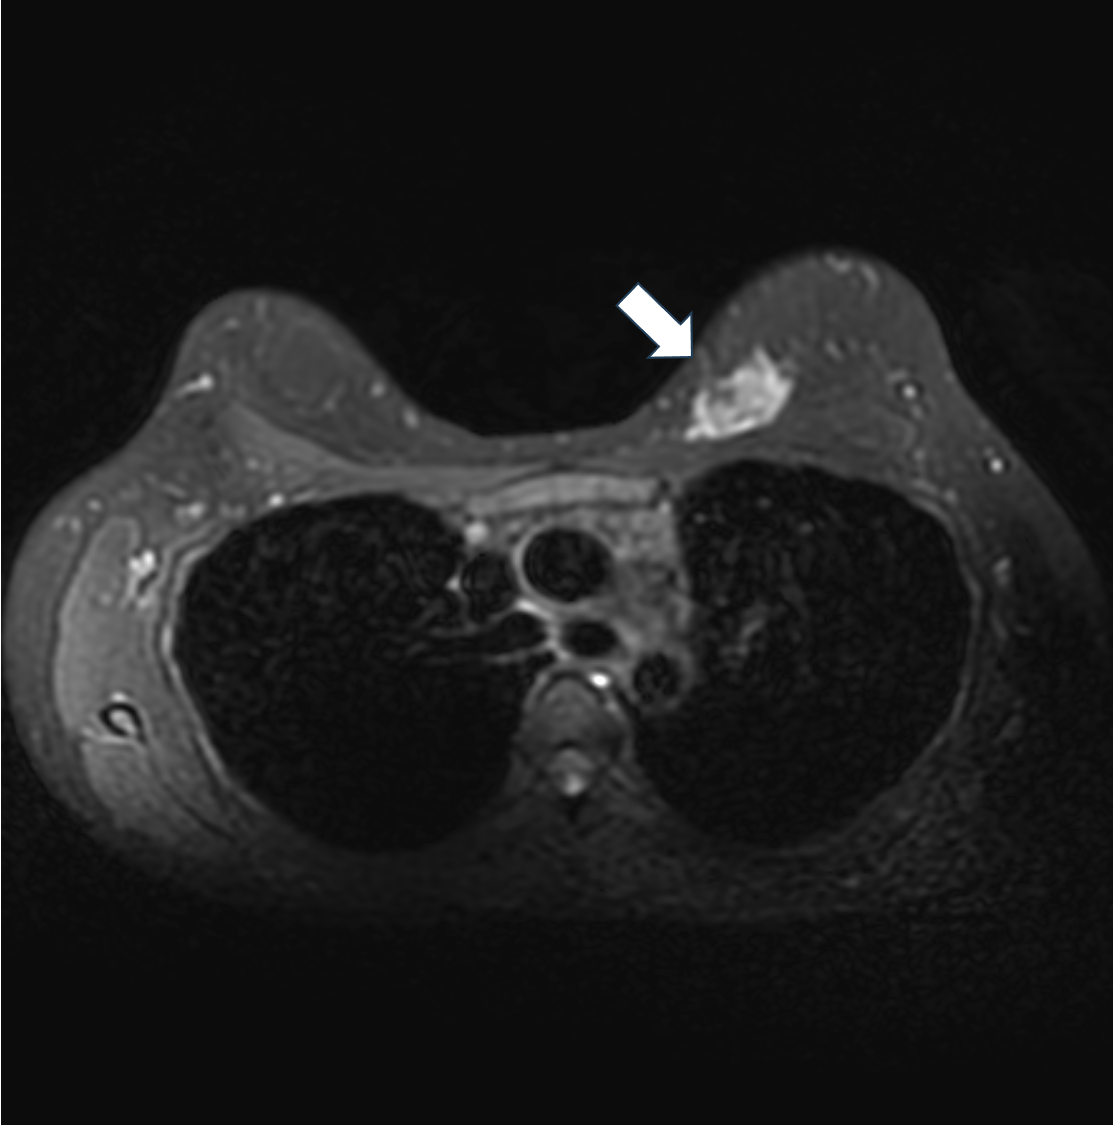

3. 拡散強調画像 b=1000(s/mm2)(造影前)

拡散強調像では明瞭な高信号を示す。細胞密度の高い腫瘍が示唆される。